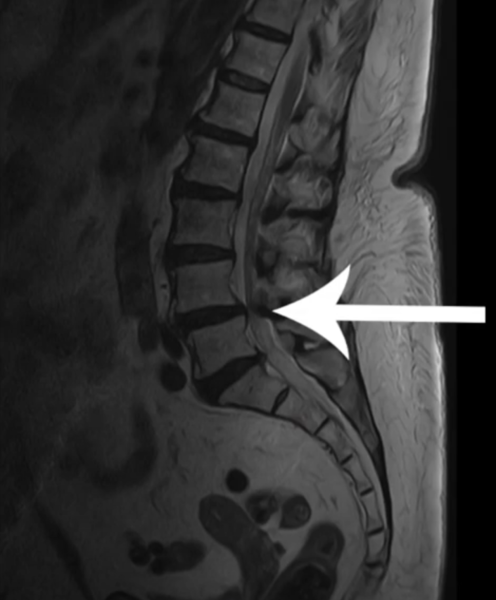

Пациентка 76 лет обратилась с диагнозом спондилолистез и стеноз поясничного отдела позвоночника на уровне L4-L5 (позвонков 4-5). Целенаправленно пришла в клинику за оперативной помощью, зная диагноз, прочитав про лечение.

Если вспомнить, ситуация была такая: вы пришли, сказали, что все знаете. Снимки подтвердили дегенеративный спондилолистез и стеноз на L4-L5. Причем стеноз абсолютный - позвоночный канал был 6 мм. Вы сразу согласились на обследование, прошли его и затем согласились на операцию.